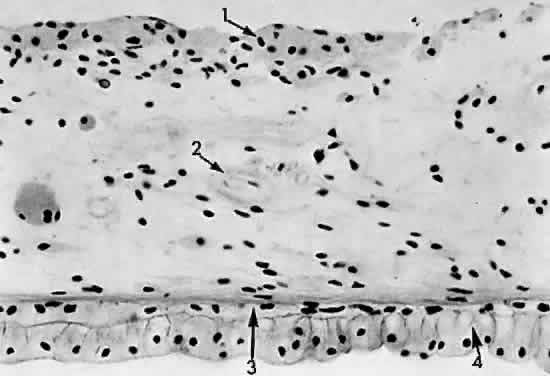

The pars plana is a 4-mm flat band area extending posterior to the ciliary processes. It joins with the peripheral cystoid retina at the ora serrata (Fig. 13). The nonpigmented epithelial layer flattens anteriorly but becomes columnar posteriorly as it approaches the retina. The pigmented epithelial layer of the pars plana continues as the pigmented epithelium of the retina. A ridged cuticular layer (the reticulum of Muller) lying adjacent to the pigmented epithelium layer of Bruch's membrane at the ora serrata is an avascular connective tissue that separates the inner cuticular layer from the outer elastic layer of Bruch's membrane in the pars plana region (Fig. 14).

Fig. 14. Pars plana: 1, nonpigmented epithelium; 2, pigmented epithelium; 3, cuticular layer of Bruch's membrane; 4, avascular connective tissue layer; 5, elastic layer of Bruch's membrane; 6, vascular layer of pars plana (× 225, KEI 8982B).

The nonpigmented epithelium of the pars plana secretes the acid mucopolysaccharide component of the vitreous body at its basal attachment. The lens zonules are firmly attached to the nonpigmented epithelial cells of the pars plicata, so that during cataract surgery traction may cause detachment of the nonpigmented epithelium if the zonules are broken.